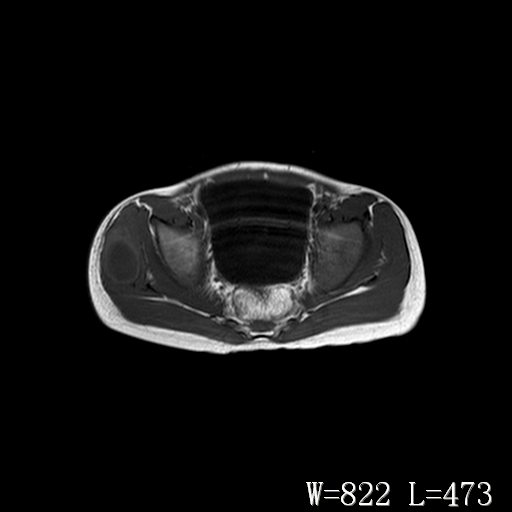

男,6岁,发现右臀部肿块10余天。

右侧臀部较大囊性肿块,长t1、长t2信号改变,周围组织信号正常,不知有否局部注射史?如果有,则支持脓肿,否则要考虑血管瘤可能。